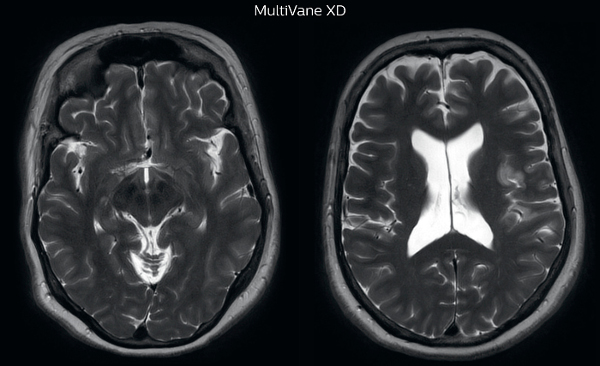

“Motion artifacts can obscure subtle findings, make image interpretation more difficult and decrease diagnosis confidence. For example, when imaging the cerebellum or brain stem, or when looking for subtle multiple sclerosis (MS) lesions, motion can be problematic,” says Dr Nickerson. MultiVane XD motion-free imaging delivers diagnostic images even in the case of severe patient motion. A more relevant patient group is one with typical small artifacts related to moderate motion like an occasional cough. The absence of those artefacts brings forth better day-to-day diagnostic confidence. MultiVane XD works in multiple orientations and for various contrasts, such as T1-weighted, T2 weighted and FLAIR. Trevor Andrews, PhD, explains that the team compared motion artifacts seen in the brain with MultiVane XD and with T2-weighted TSE. “In nine out of the ten datasets in our studywe saw clear improvementswith MultiVane XD, while in the tenth dataset image qualitywas comparable. The MultiVane XD sequence is now used in the majority of patients that present at UVM for brain MRI.”

“We saw MultiVane XD provide remarkable improvement, not only for artifacts caused by patient motion, but also for the extent of pulsation artifacts in the basal cisterns. Based on these results, we have added the MultiVane XD sequence to our brain studies,” says Dr. Nickerson. “MultiVane XD is especially useful when imaging patients with diseases that cause white matter changes on T2-weighted images, such as MS, small vessel disease, vasculitis and sarcoidosis,” says Dr. Nickerson. “Many of these are only visible on T2-weighted or FLAIR images, and sometimes aren’t even seen with FLAIR images. However, when using MultiVane XD and we don’t see any motion on the rest of the scan, but still do see a signal abnormality, we can probably attribute that to a real disease process, rather than an artifact.”

The images made with MultiVane XD show significant reduction in motion artifact compared to the T2-weighted images without MultiVane below them. Scanned on Ingenia 3.0T